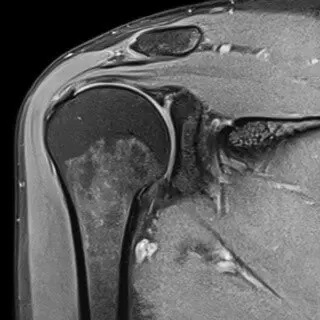

Проведенное на следующий день МРТ колена показало повреждение мениска. Если быть точным — разрыв (расслоение) заднего рога мениска. Это все, что смогли найти на МРТ.

Оказалось, имел место гемартроз – скопление крови в суставе. Сустав был напряженный и болезненный при пальпации. Рентген сустава не выявил особой патологии. УЗИ сустава показало признаки отека и ущемления синовиальной оболочки. Самые главные находки меня ждали при т.н. физикальном (клиническом) обследовании сустав. Обнаружилась травма связок колена. Но, самое главное в этой истории оказалось то, что была сохранена двигательная функция сустава. Иными словами, «порванный» мениск не блокировал сустав, его подвижность не была нарушена. Это давало шанс на лечение колена без операции.

Расслоенный задний рог мениска, который первым бросается в глаза при МРТ обследовании может оказаться случайной находкой, не имеющей никакого отношения к боли в колене. Как это случилось с Людмилой (см. начало статьи).

Кстати, откровенный разговор с радиологами Центра «Меддиагностика» дал неожиданные даже для меня результаты. Оказалось, что так называемый разрыв (расслоение) заднего рога мениска выявляется в 8 из 10 обследованных на МРТ коленей. Сегодня эту находку мы не расцениваем, как патологию, которая нуждается в операции. Если внимательно и с пониманием предмета поискать, как правило, можно найти иную, реальную, причину боли. Тем более, что мениск не иннервирован и не болит сам по себе.

МРТ суставов очень информативный метод. Но без клинического анализа он может стать источником гипердиагностики. Как это произошло с Людмилой (см. выше). Но, у МРТ есть неоспоримое достоинство. С его помощью можно найти много неожиданного в суставе.

NB! МРТ обследование при болях в суставах полезно только в сочетании с клиническим осмотром, опросом и тестированием сустава. Именно осмотр доктора позволяет сформулировать объем и характер обследования. МРТ подтверждает (или нет) клинические находки доктора.